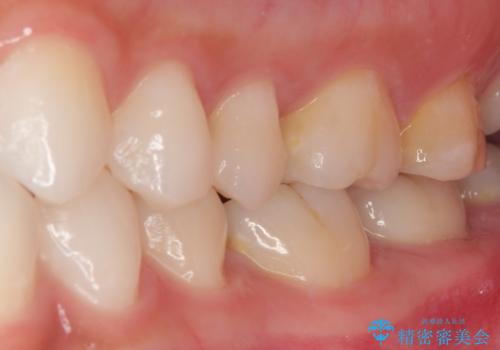

見た目、機能面共に大変喜んでいただきました。

精密な型どりを行った被せものは適合性も良いため虫歯の再発リスクを低減することが可能です。